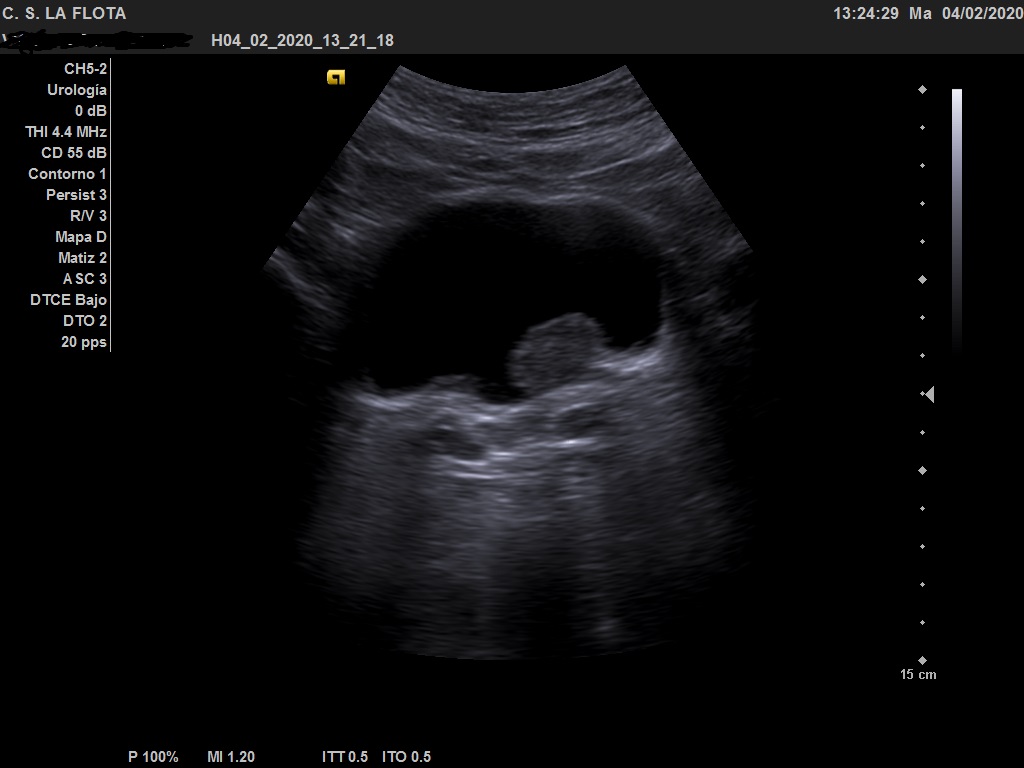

Ecografía clínica: riñones de tamaño y morfología normal, con buena diferenciación corticomedular y sin dilatacion de vias. En vejiga lesión polipoidea  de 25*18 mml.

Ante los hallazgos ecográficos se derivó al paciente a urología con copia de las imágenes. En urología solicitan cistoscopia sin precisar más pruebas de imagen.